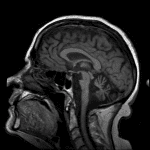

Cerebellar ataxia-type multiple system atrophy (MSA-C)

Sample ReportMarked pontocerebellar atrophy out of proportion to relatively mild supratentorial parenchymal volume loss. In combination with the finding of cruciform T2 signal hyperintensity in the pons at the level of the middle cerebellar peduncles (“hot crossed bun” sign), this appearance is most suggestive of cerebellar ataxia-type multiple system atrophy (MSA-C).